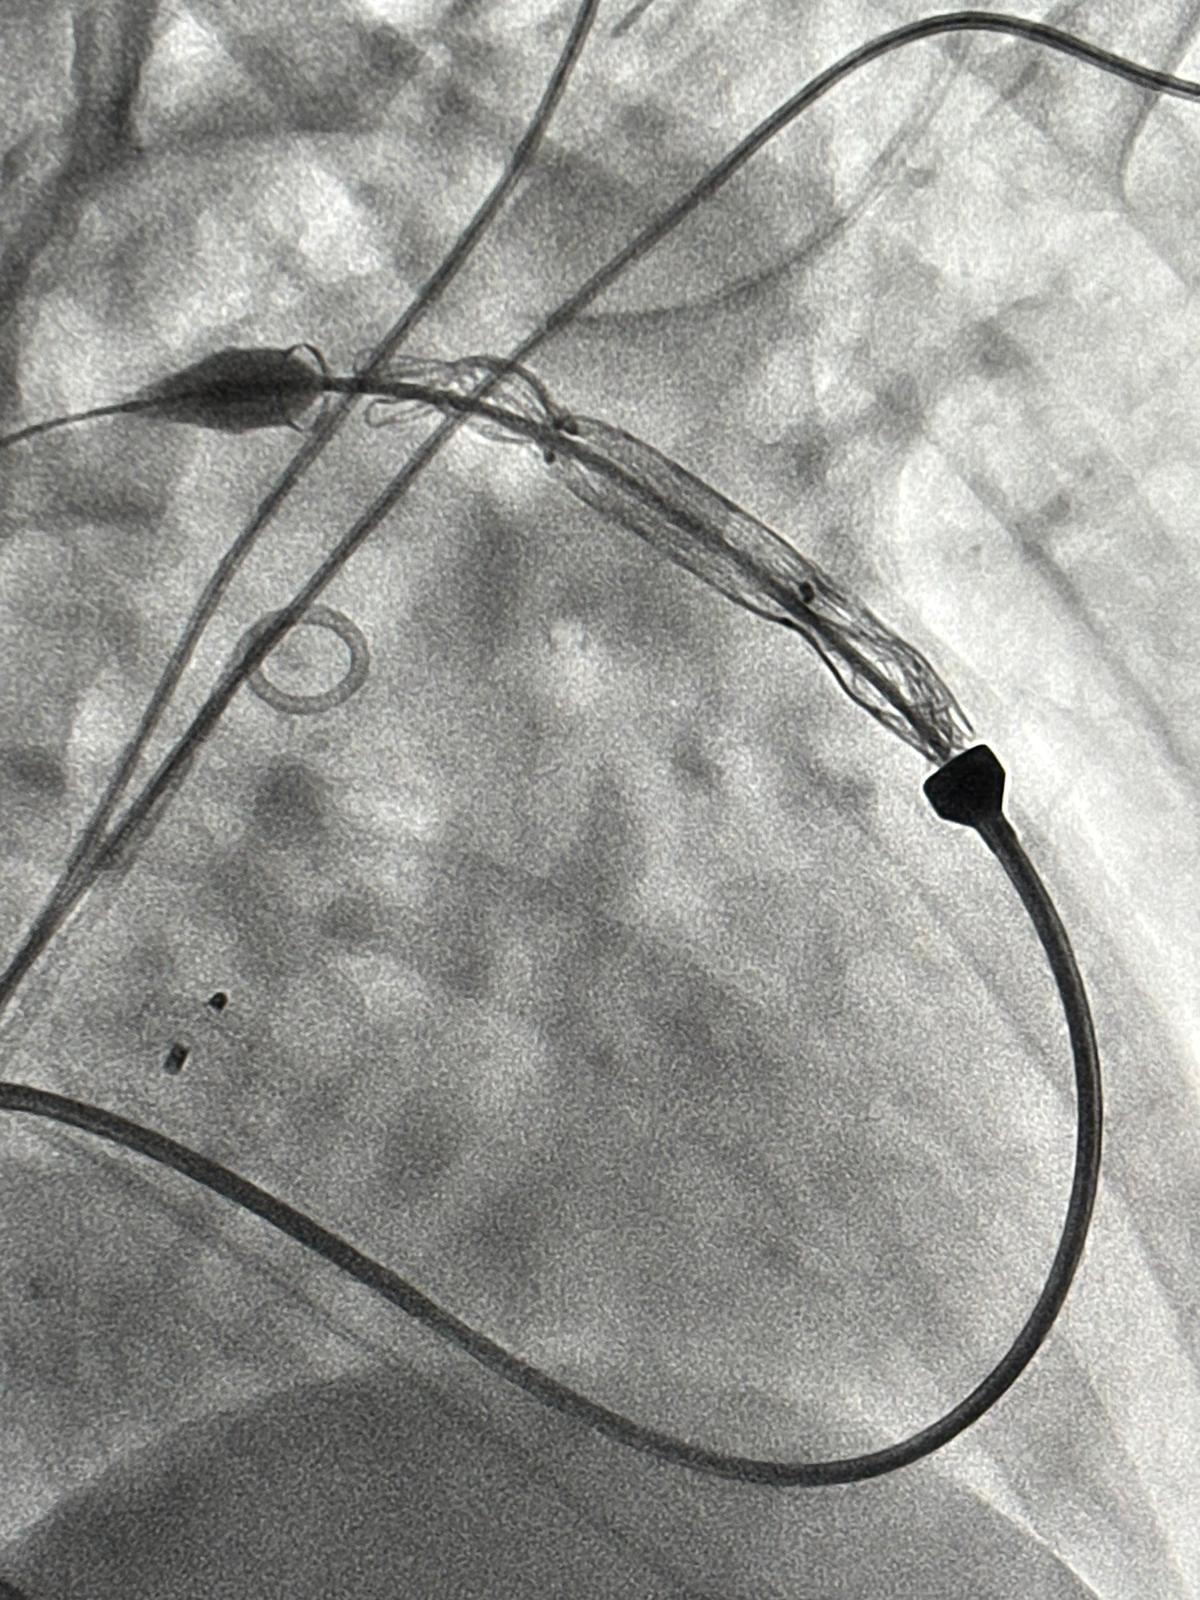

Pierwszy w UCK zabieg przezskórnej implantacji zastawki tętnicy płucnej typu Venus przeprowadzono 6 listopada u pacjentów po korekcji zespołu Fallota (złożonej siniczej wady serca), u których doszło do istotnej dysfunkcji zastawki tętnicy płucnej. Kolejny, bardzo rozległy zabieg kardiochirurgiczny obarczony byłby bardzo wysokim ryzykiem. Zabieg przeprowadzony był w Pracowni Kardiologii Inwazyjnej I Kliniki Kardiologii UCK przez prof. Roberta Sabiniewicza z Katedry i Kliniki Kardiologii Dziecięcej i Wad Wrodzonych Serca GUMed i dr. hab. Radosława Targońskiego z I Katedry i Kliniki Kardiologii GUMed przy udziale eksperta w stosowaniu tej metody leczenia – prof. Sebastiana Górecznego z Kliniki Kardiologii Dziecięcej USD w Krakowie. Znieczulenie ogólne prowadzone było przez dr. Macieja Kuklińskiego z Kliniki Anestezjologii i Intensywnej Terapii GUMed, UCK.

Zabiegi przebiegły bez powikłań i zakończyły się sukcesem. Kilka dni później, po badaniach kontrolnych, pacjenci zostali wypisani do domu. Na ten sukces pracował zespół kierowany przez prof. Joannę Kwiatkowską z Kliniki Kardiologii Dziecięcej i Wad Wrodzonych Serca GUMed, UCK, a w szczególności lek. Sebastian Ciemny i dr Lidia Woźniak-Mielczarek. Na zabiegi czekają już kolejni pacjenci, u których wiele lat po korekcji złożonej wady serca doszło do powstania istotnej niedomykalności zastawki tętnicy płucnej.